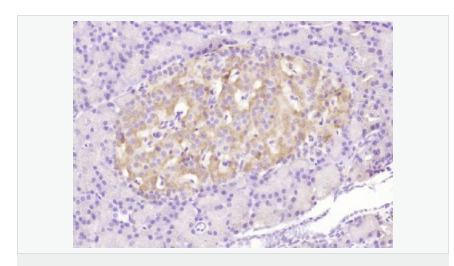

| 产品应用 | WB=1:500-2000 ELISA=1:5000-10000 IHC-P=1:100-500 Flow-Cyt=3μg /test (石蜡切片需做抗原修复) not yet tested in other applications. optimal dilutions/concentrations should be determined by the end user. |

| 免 疫 原 | KLH conjugated Synthesised phosphopeptide derived from human Bax around the phosphorylation site of Ser184:TA(p-S)LT |